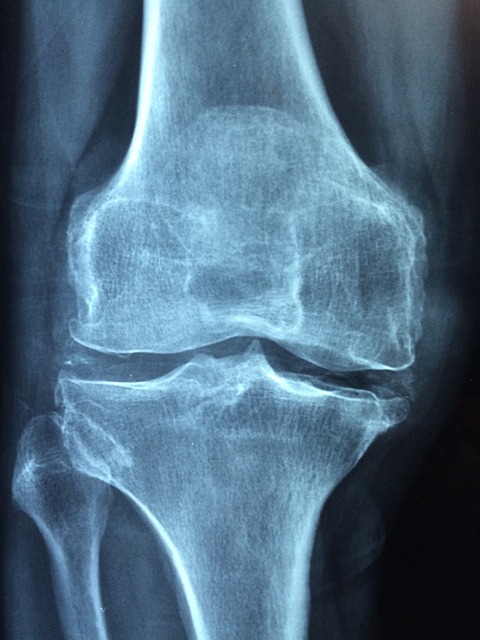

- 영상검사: 엑스레이, 초음파, MRI를 이용해 관절의 염증 상태를 확인합니다.